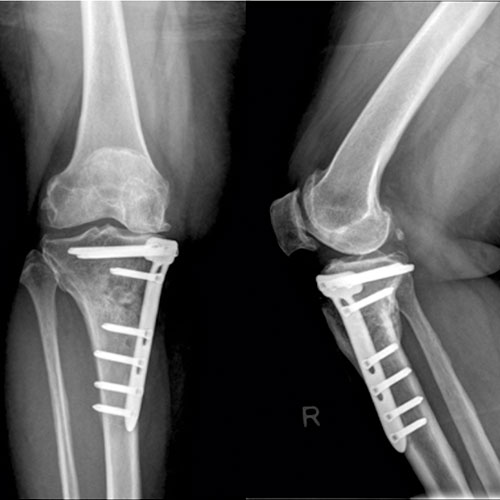

Fracture treatment and Surgery, including management of Non-union, Deformity Correction and Bone Infection Treatment

Replacement Surgeries including Partial and total knee replacements, hip replacements as well as complex knee and hip replacements

Procedures such as ACI, HTO, arthroscopy and stem cell therapy for AVN that maintain the health and function of your joints